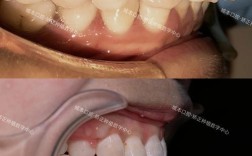

拔牙矫正牙齿数量是正畸治疗中一个核心且备受关注的问题,许多患者对“拔牙”存在恐惧心理,担心牙齿数量减少会影响口腔功能或美观,拔牙矫正并非“减少牙齿”,而是通过科学计算拔除部分牙齿,为剩余牙齿的排列和咬合关系的调整创造空间,最终实现健康、稳定、美观的矫治目标,拔牙数量的确定需要综合患者的口腔实际情况、骨骼发育、软组织侧貌等多方面因素,并非“拔越多越好”或“越少越好”,而是“恰到好处”的个体化方案。

拔牙矫正是正畸治疗中常见的手段,其核心目的并非单纯减少牙齿数量,而是解决口腔中存在的多种问题:

- 解决牙齿拥挤:当牙弓长度不足以容纳所有牙齿时,会导致牙齿排列不齐、重叠、扭转(即“拥挤”),通过拔除部分牙齿,可释放牙弓空间,使剩余牙齿排列整齐,拥挤度超过10mm时,通常需要拔牙才能有效解除拥挤。

- 改善面部软组织侧貌:对于上颌前突(“龅牙”)或双颌前突的患者,拔牙后可通过内收前牙,减少唇部突度,使面部轮廓更协调美观。